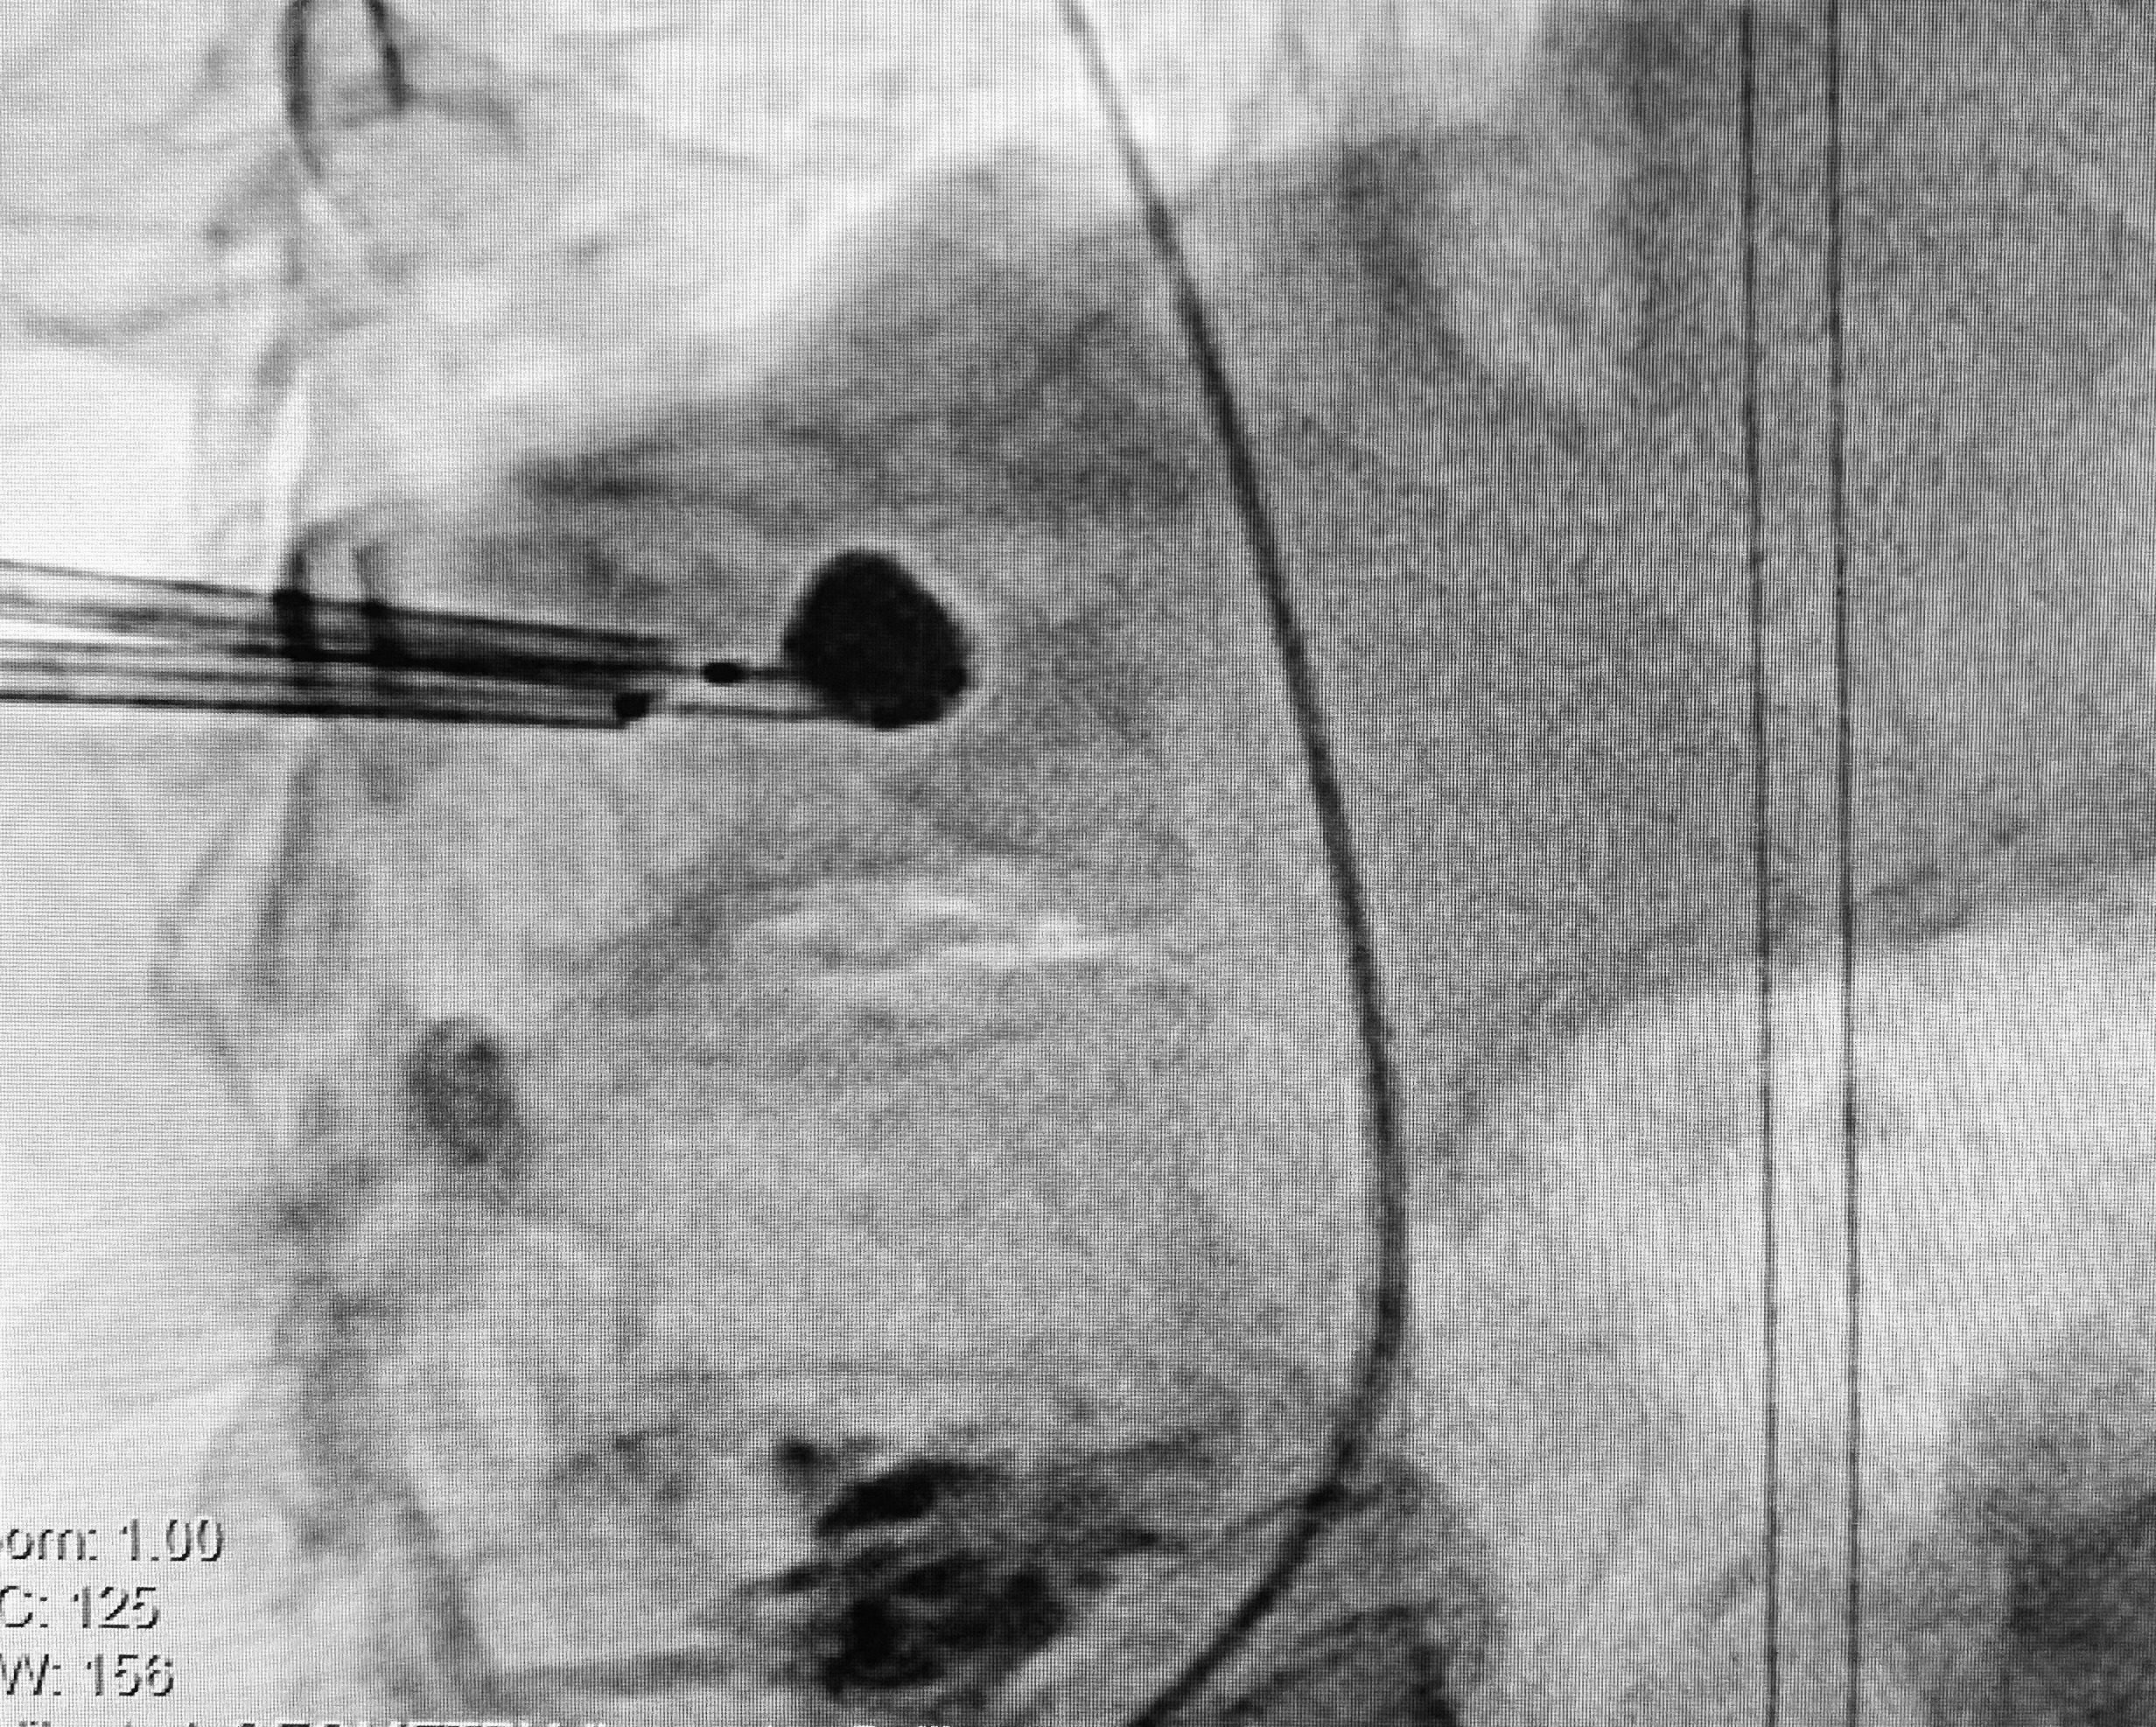

Interventional radiology is an innovative and exciting field in which the interventional radiologist uses image guidance and minimally invasive tools to perform procedures. Procedures that would otherwise require open surgery.

Decrease the side effects of surgical intervention, like bleeding and scarring. By using less invasive devices like catheters and wires, we avoid many complications that arise with open surgery.

Interventional radiology can treat many diseases and alleviate pain, from pelvic pain to varicose veins to musculoskeletal pain. Since the procedures are less invasive than traditional surgery, recovery is often less painful.

Treat your condition with a minimally invasive approach. We perform common interventional radiology procedures, including treatment for uterine fibroids, cancer, peripheral arterial disease (PAD), varicose veins, and more.